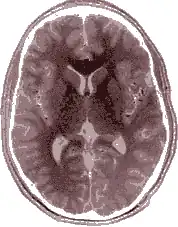

Le cerveau, bien que grossièrement symétrique d'un point de vue morphologique, est en réalité latéralisé tant du point de vue de certains détails anatomiques que sur le plan fonctionnel. On parle d'asymétrie cérébrale. Les deux hémisphères ne jouent pas un rôle identique : d'une part, en raison de la décussation des voies nerveuses, chaque hémisphère traite les informations en provenance et à destination de la moitié contralatérale du corps ; d'autre part, dans le domaine particulier du langage, il y a en général dominance de l'hémisphère gauche sur le droit.

Être latéralisé est une caractéristique des animaux qui se servent préférentiellement d'une seule main : c'est être gaucher ou droitier. Le fait d'être habile des deux mains est l'ambidextrie. Le cerveau humain (et à un moindre degré celui des autres vertébrés) est anatomiquement à peu près symétrique de sorte qu'un des deux hémisphères est symétrique de l'autre hémisphère. Cependant, il existe une importante dissymétrie fonctionnelle : chaque hémisphère prend en charge certaines tâches qui lui sont peu ou prou spécifiques ; on parle de spécialisation hémisphérique. Dans le cas des sujets qui sont droitiers homogènes (droitiers pour la main, le pied, l’œil et l'oreille), l'hémisphère gauche a un rôle essentiel pour les gestes précis, intentionnels, bien catégorisés ; on dit qu'il s'agit de l'hémisphère digital. L'autre hémisphère plus spécialisé dans la gestion du corps au service des intentions visées par l'hémisphère digital, gère les données plus globales, plus imagées ; il est qualifié d'hémisphère « analogique ».